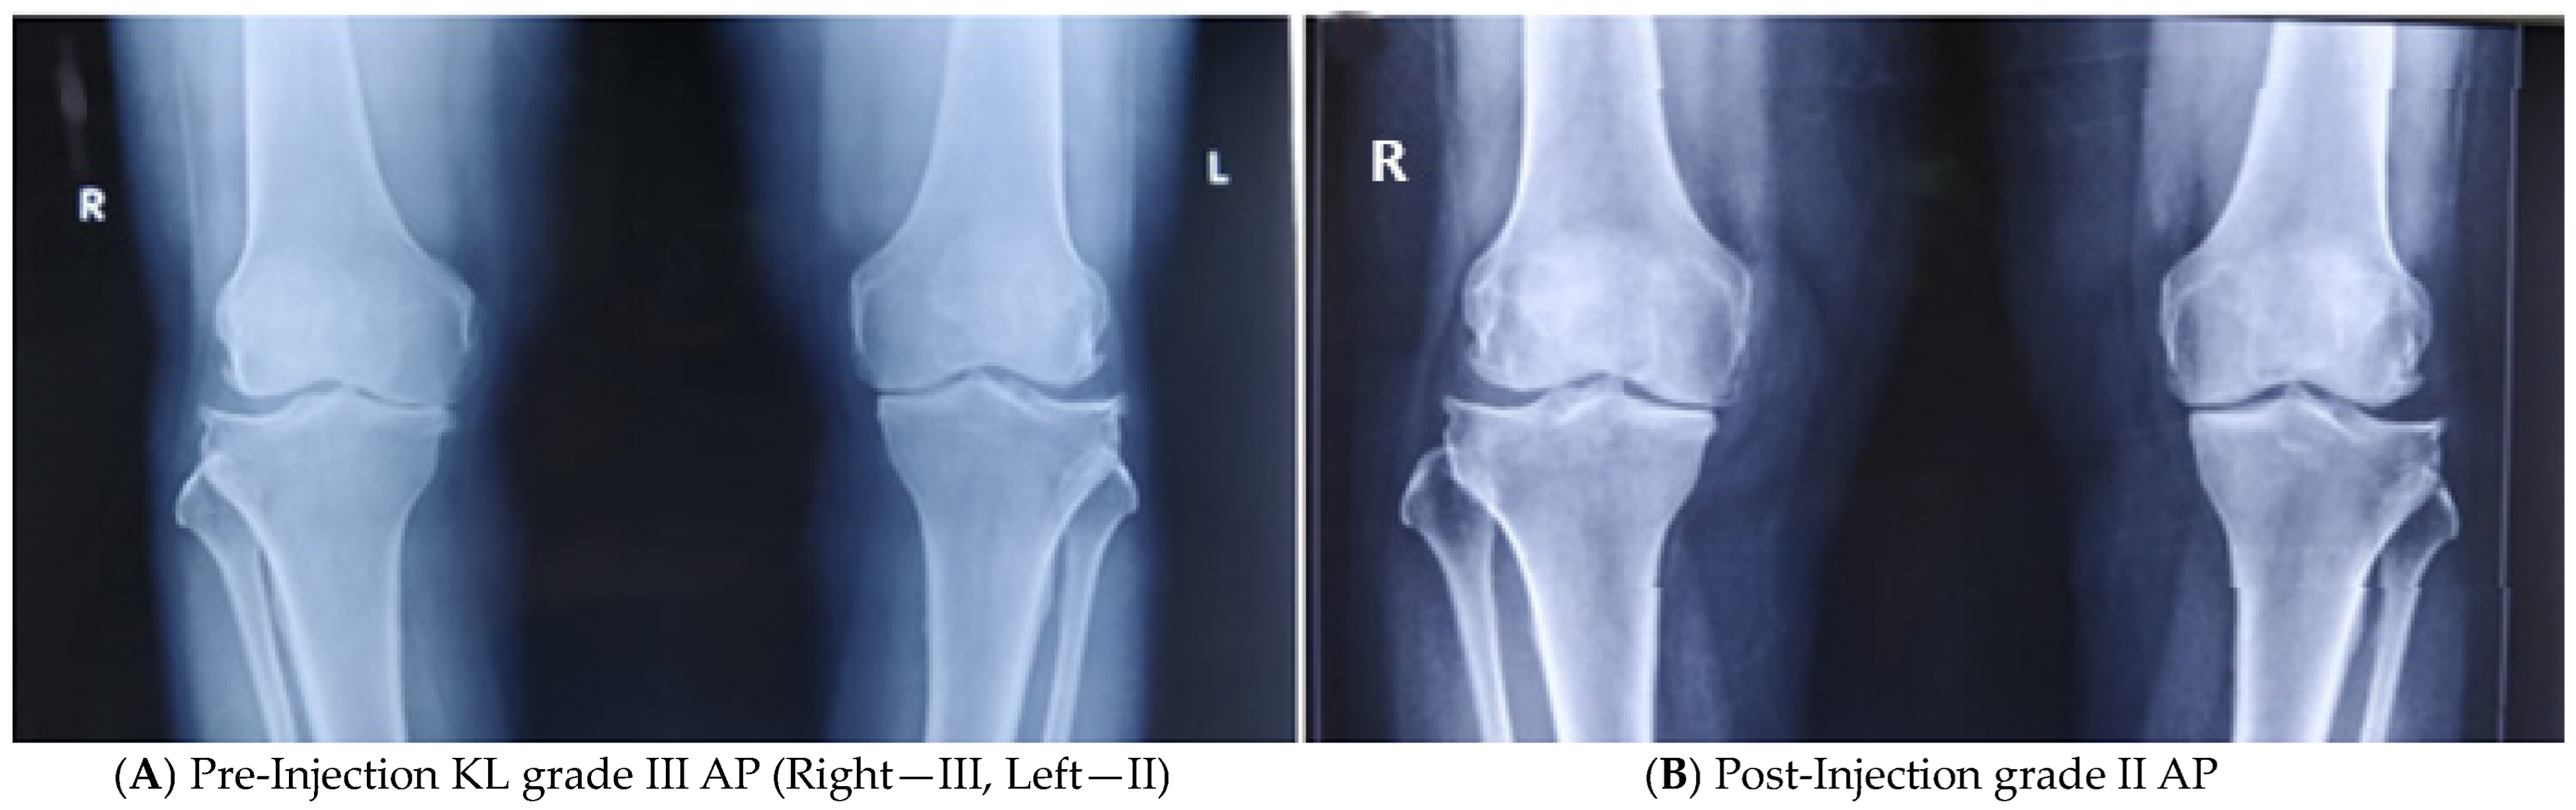

3.4. Objective Assessment